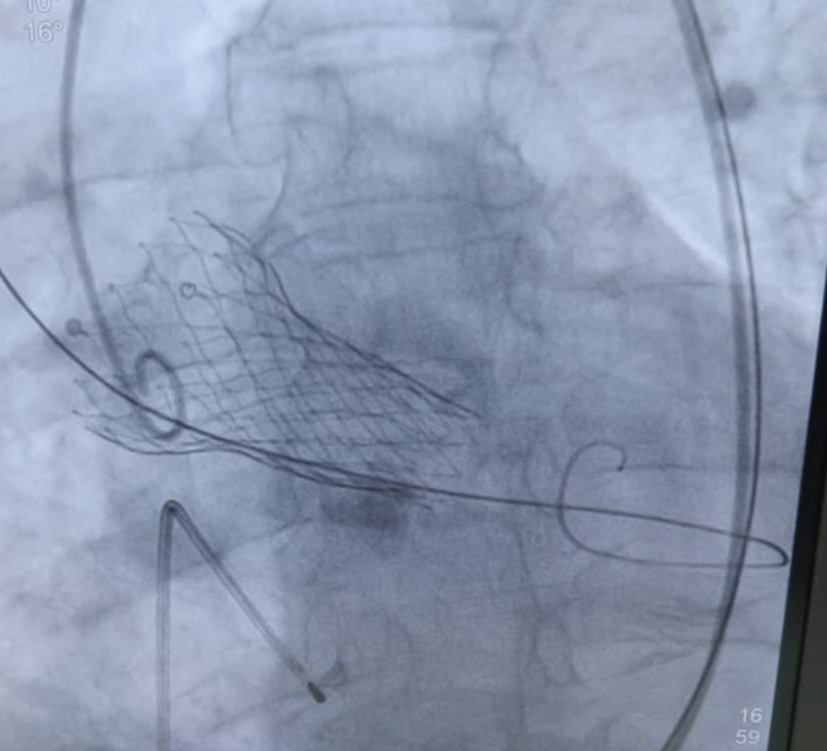

أعلن الدكتور عادل تعيلب، مدير هيئة الرعاية الصحية ببورسعيد، نجاح زراعة صمام أورطي نسيجي عن طريق القسطرة بمستشفى النصر التخصصي التابع لمنظومة التأمين الصحي الشامل، وذلك لمريض يبلغ من العمر 73 عاما يعاني من ضيق حرج في الصمام الأورطي.

كان المريض يعاني لفترة طويلة من صعوبة شديدة في التنفس مع أقل مجهود بالإضافة إلى أن المريض متعافي حديثا من كسر مضاعف في منطقه الحوض، وتكمن صعوبة الحالة في الوضع التشريحي الأفقي لجذع الشريان الأورطي، وتم إجراء العملية بنجاح لمهارة الفريق الطبي واستخدام أحدث الأجهزة وطرق العلاج بمستشفيات الهيئة.